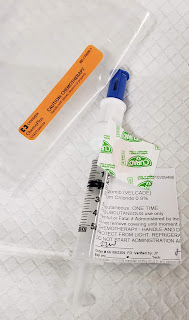

2- Next I agreed to begin the Vintage chemo Cytoxan with my Velcade and Dex steroids... only I am going to Cheat... ssshhhh don't tell my Dr yet, but no way am I downing 8 frikn Cytoxan pills at one time! I asked her for a lower dose, and she was kind enough to lower the standard of 10 Cytoxan pills to 8, but after I picked up the Rx, and saw them, and began to visualize ingesting all of them at once!... I'm Helllllllooooo, Noooooo, I'm not going to put all those in me at once, risking a nasty GI backlash! I know, I know, I'm a Cancer Patient with Incurable High Risk Myeloma, and I should be on board for high dose- kill off those super strong myeloma cells trying to kill me!! Well, yes, but No! At this point in my life, and treatment.... Quality of Life, and lessening the chance of feeling gross and sick, is my main priority! Yes my myeloma is 4 Times the High End of Normal right now... but sorry, I just can't stand the idea of getting grossly GI sick. See way baaaaaack in June 2010 I had "that reaction" to IV Cytoxan, and uuggghhhh, nope, no thank you... not again, if possible. So Tomorrow Night, Oct 29, after taking 40mg Dex steroids in the morning, my weekly Velcade shot in the afternoon, I will very tentatively, unbravely take 4, yes four of the 8 Cytoxan pills!

Hello pretty blue Cytoxan pills!

Blue just like my lil blue Bug...

Would you take 8 or 10 of these at a time?

I'm also armed with Zofran, but I don't think I'll "pregrame" with that just yet, as I'll be on the high dose, 40mg Dex steroids, and that should help with any nausea, right?? Suggestions please!!!, if you've done this combo, which most of the Myeloma patients have, early on! Why didn't I?? I was concerned about all the warnings from myeloma patients about BAD Neuropathy from Velcade, so I skipped over to Kyprolis, and never had the Cytoxan pills added in, as Kyprolis Dex worked for me for about 10 months, then Darzalex, Pomalyst, Dex worked for me for about 18 months, so here I am, going backwards to meds I skipped, before I'll do clinical trials, CAR T, etc. Yes, no matter how "bad" my situation becomes, Quality of Life is first and foremost to me... since what's the point of treating myeloma, if I'm so sick all the time, I'm not living. Isn't the point of treatment to give a cancer patient their life back??? I've been doing this for almost 9 years now, and for so many hours, days, weeks, months, etc, my life has been so limited by side effects, I learned that for me, the treatment has to make sense... kill the cancer cells, but let me see the sunshine too!

And I'm still laughing about the amount of Meds I'm needing to take to keep me ALIVE! Here's to Velcade, new Cytoxan, Dex steroids, Mepron/Atovaquone, Acyclovir... just to name a few LOL

40mg Dexamethasone steroids- 10 pills

400mg Cytoxan chemo- 8 pills

200mg Acyclovir- 1 pill

and other Vitamins, pain meds, Thyroid daily pill....

Hello weekly Velcade shots